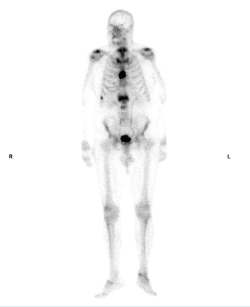

Cuando la enfermedad se confirma, el último paso es definir los focos de actividad de la enfermedad, siendo la gammagrafía(5)(Figura 4) la prueba elegida con esta finalidad; en este paciente mostró focos activos a nivel dorsolumbar, pélvico y en las costillas 7.a y 8.a.

Figura 4. Gammagrafía.